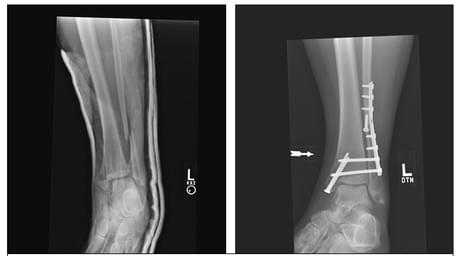

Удаление пластины после операции

Пластинами и винтами фиксируют практически любые кости человеческого тела. Это очень надежный и удобный метод остеосинтеза. На сегодняшний день существуют огромное количество пластин различной формы, размеров и модификации для определенного вида перелома. Самые распространенные примеры остеосинтеза пластинами это:

- Остеосинтез ключицы;

- Остеоситез плечевой кости

- Остеосинтез наружной лодыжки;

- Остеосинтез переломов голени;

- Остеосинтез пястных и плюсневых костей;

- Остеосинтез лучевой и локтевой кости.